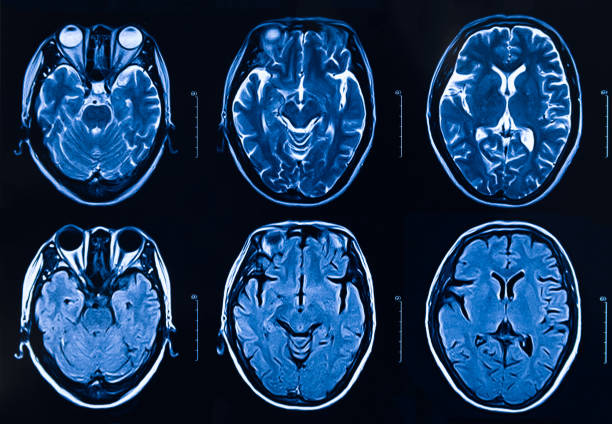

뇌 일부분에 혈액이 제대로 공급되지 않으면 혈관이 막히거나 터지기 때문에 뇌가 손상되며 여러 이상이 발생할 수 있는데 이러한 증상을 일컬어 뇌졸중이라고 합니다. 뇌졸중을 유발하는 원인에는 비만, 불규칙한 생활습관, 고혈압, 흡연 등으로 유발될 수 있으며 나타나는 전조증상들이 어쩌면 가볍게 넘길 수 있는 증상들이 많다보니 단순히 노화로 인한 증상으로 가볍게 여기는 경우도 있기 때문에 초기 대응이 어렵습니다. 따라서 이번 시간을 통하여 뇌졸중 전조증상에 대해 자세히 알아보고 초기 대응력을 높이시기 바랍니다.